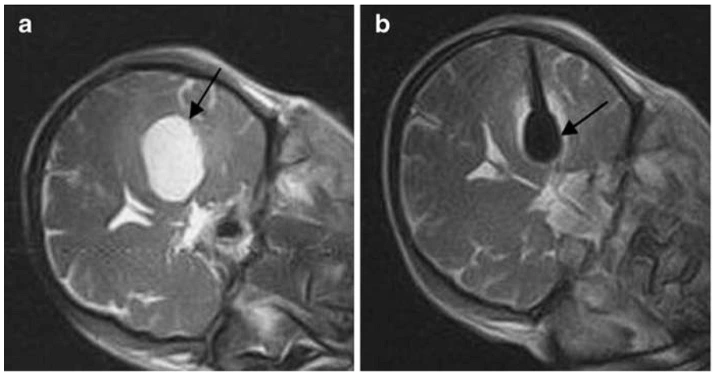

通过-140℃极冷冻结和+45℃快速复温的交替循环,在微创条件下精准杀灭肿瘤细胞,保护周围健康组织。

实时影像监测冰球范围,精确控制治疗区域,最大程度保护正常组织和重要器官

以肾癌为例(Cryoablation for Small Renal Masses: Selection Criteria, Complications, and Functional and OncologicResults)